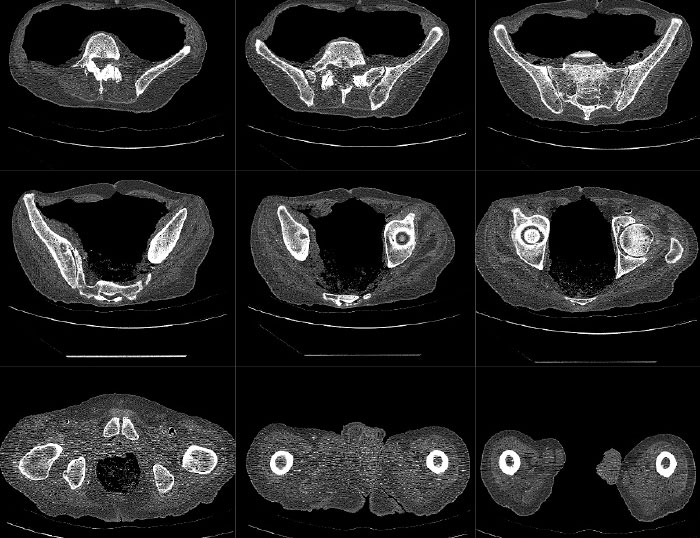

Mako robotic-arm assisted technology provides you with a personalized surgical plan based on your unique anatomy. First, a CT scan of the diseased joint is taken. This CT scan is uploaded into the Mako system software, where a 3D model of your hip is created. This 3D model is used to pre-plan and assist your surgeon in performing your total hip replacement.

Step 1. Hip CT Scan